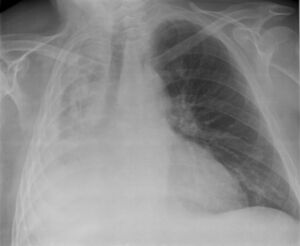

- الأشعة السينية للصدر (الانخماص ما بعد العمليات الجراحية يظهر في الجزء الأدنى من الرئتين)

الانخماص المزمن قد يتخذ واحداً من الشكلين: إما متلازمة الفص الأوسط أو انخماص مدوّر. في متلازمة الفص الأوسط الأيمن، الفص الأوسط للرئة اليمنى ينقبض عادة بسبب الضغط على الشعب الهوائية من الغدد اللمفاوية المتضخمة أو وجود ورم أحياناً، و من الممكن أن تصاب الرئة المقبوضة المسدودة بالتهاب رئوي يفشل في التحلل تماماً ويؤدي إلى التهاب مزمن وتليف وتوسع الشعب الهوائية.